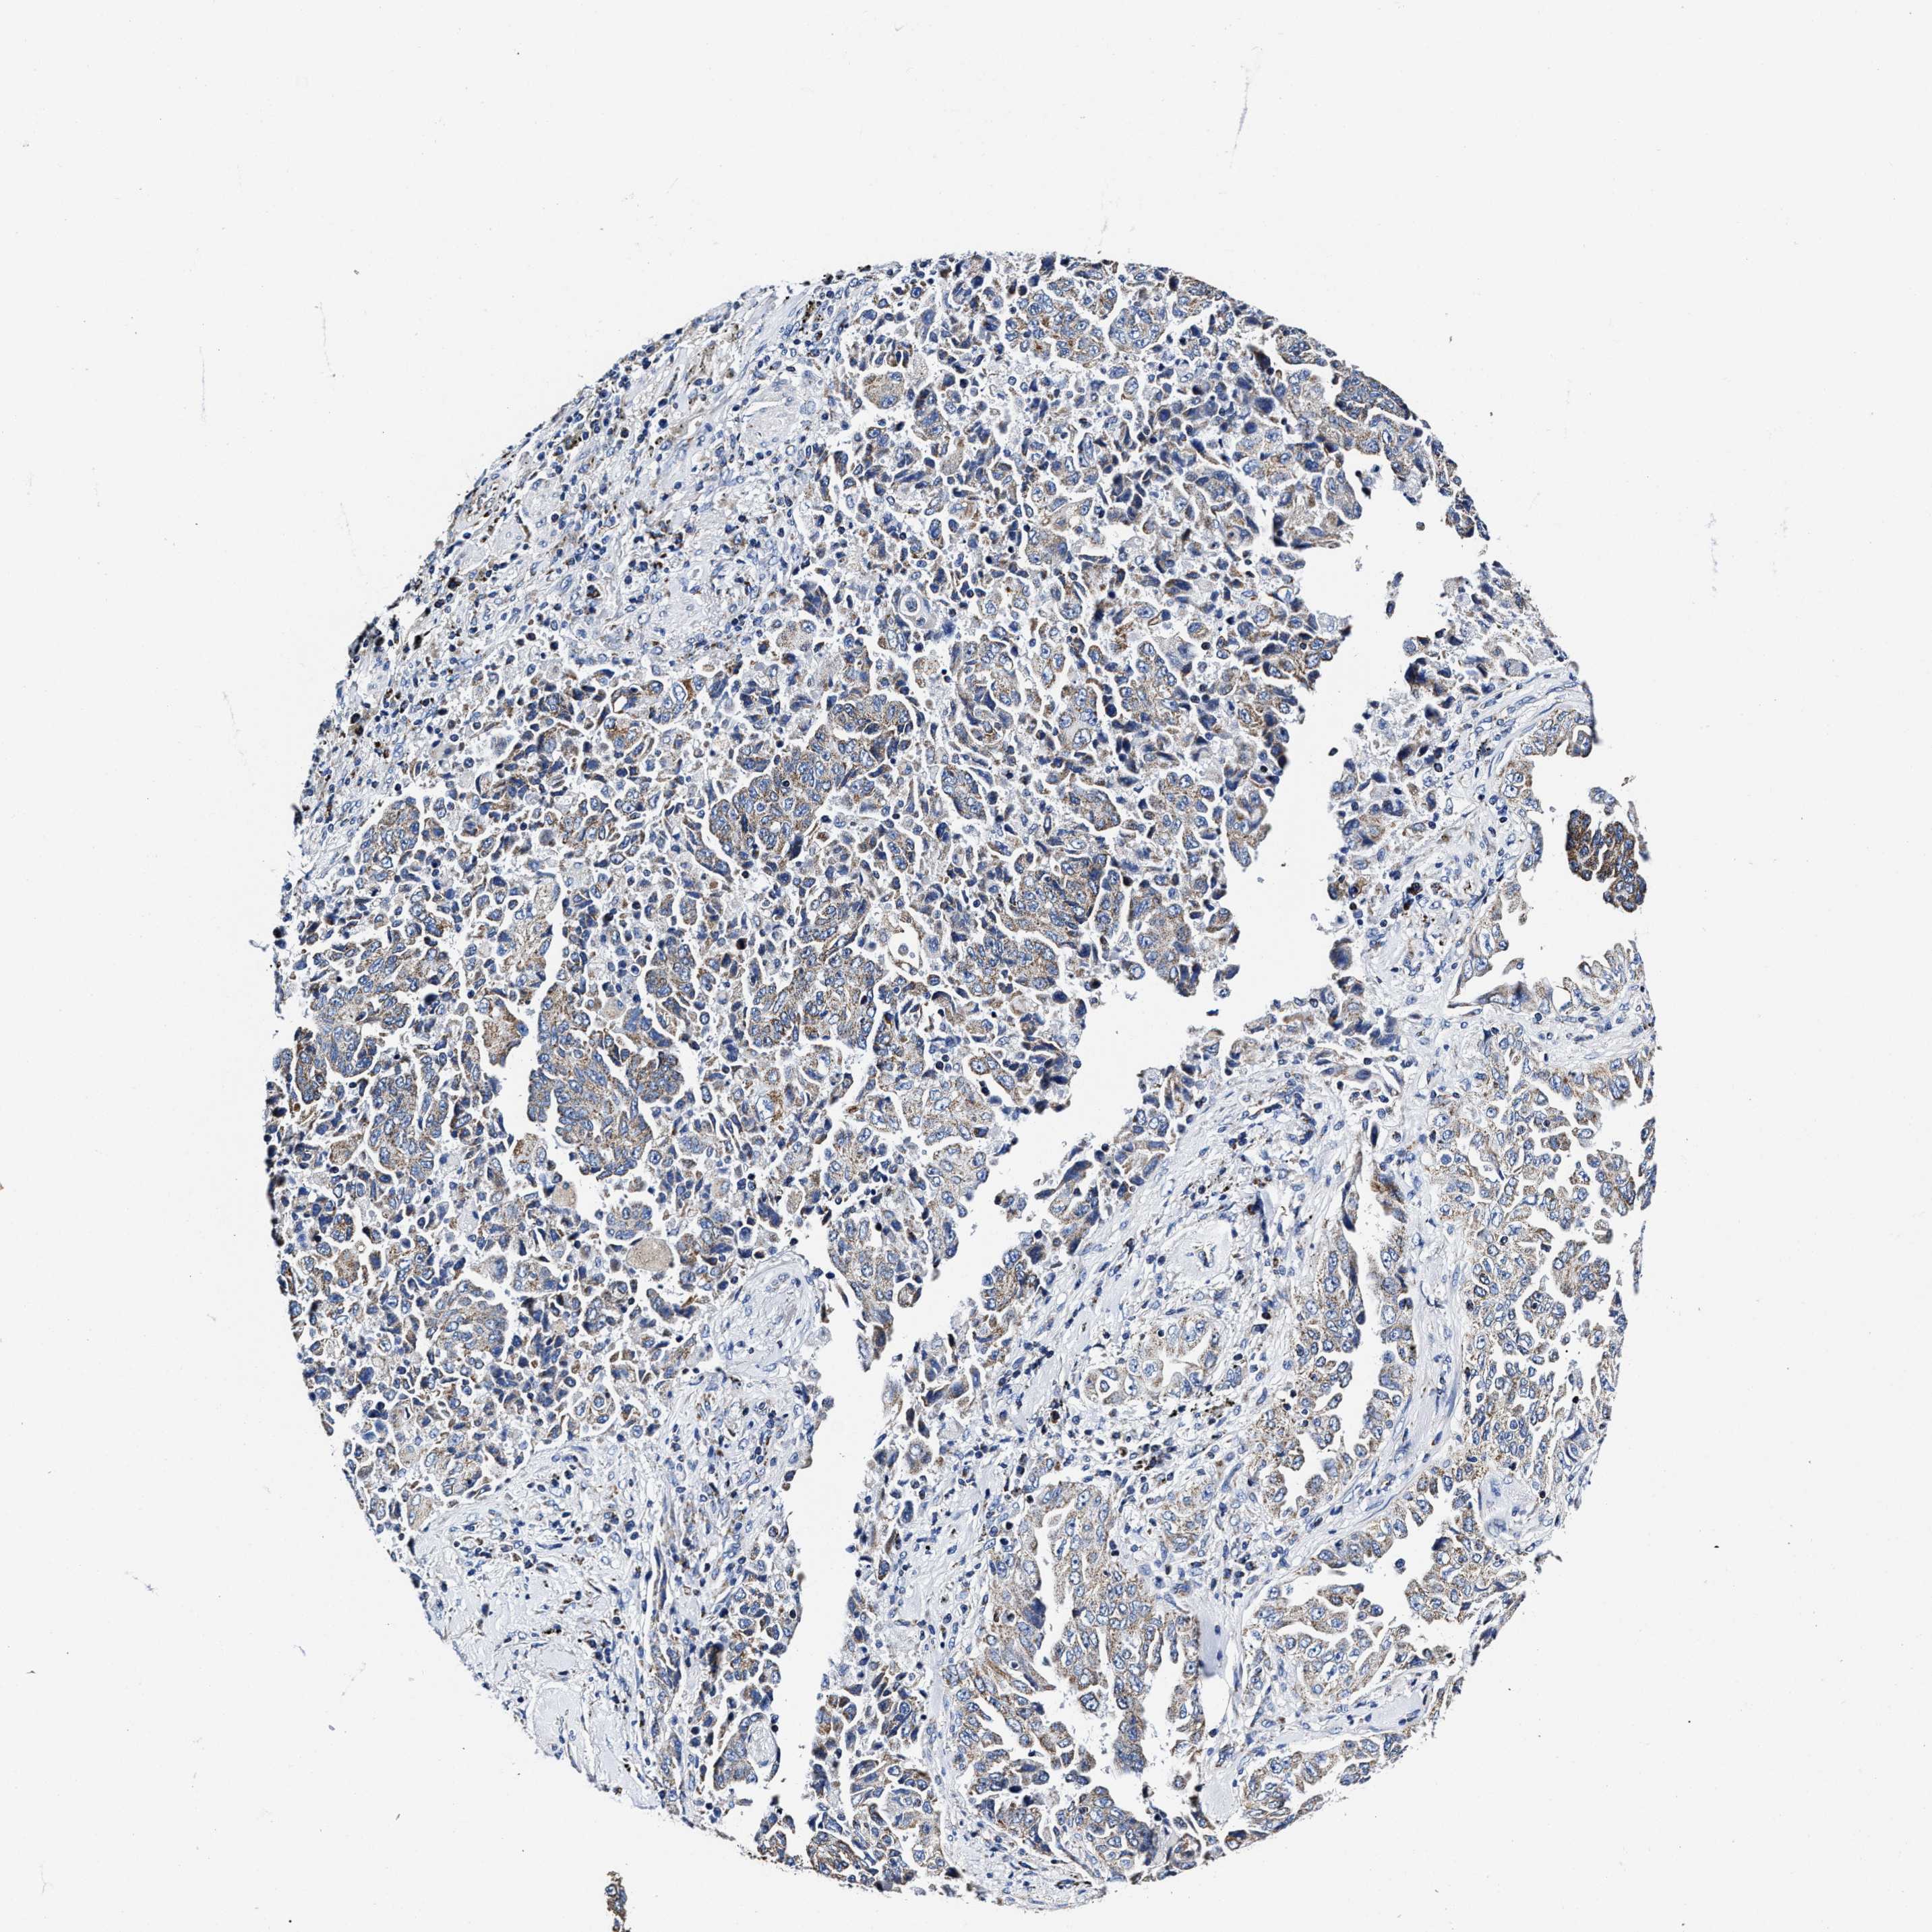

LUNG ADENOCARCINOMA (TCGA) - Interactive survival scatter ploti

The Survival Scatter plot shows the clinical status (i.e. dead or alive) for all individuals in the patient cohort, based on the same data that underlies the corresponding Kaplan-Meier plots. Patients that are alive at last time for follow-up are shown in blue and patients who have died during the study are shown in red.

The x-axis shows the expression levels (FPKM) of the investigated gene in the tumor tissue at the time of diagnosis. The y-axis shows the follow-up time after diagnosis (years). Both axes are complimented with kernel density curves demonstrating the data density over the axes. The top density plot shows the expression levels (FPKM) distribution among dead (red) and alive patients (blue). The right density plot shows the data density of the survived years of dead patients with high and low expression levels respectively, stratified using the cutoff indicated by the vertical dashed line through the Survival Scatter plot. This cutoff is automatically defined based on the FPKM cutoff that minimizes the p-score. The cutoff can be changed by dragging the vertical line or by entering a cutoff value in the square labeled "Current cut-off".

Under the Survival Scatter plot the p-score landscape (black curve; left axis) is shown together with dead median separation (red curve; right axis). Dead median separation is the difference in median mRNA expression between patients who have died with high and low expression, respectively. It is calculated as follows: median FPKM expression of dead patients with high expression - median FPKM expression of dead patients with low expression. This is intended to aid the user in visually exploring custom cutoffs and the associated p-scores and dead median separation.

Individual patient data is displayed and can be filtered by clicking on one or more of the category buttons on the top of the page. Categories describing expression level and patient information include: high, low, alive, dead, female, male and tumor stages. The scale of the x-axis can be toggled between linear and log-scale by clicking on the "x log" button. Mouse-over function shows TCGA ID, patient information and mRNA expression (FPKM) for each patient.

& Survival analysisi

Kaplan-Meier plots summarize results from analysis of correlation between mRNA expression level and patient survival. Patients were divided based on level of expression into one of the two groups "low" (under cut off) or "high" (over cut off). X-axis shows time for survival (years) and y-axis shows the probability of survival, where 1.0 corresponds to 100 percent.

HINT2 is not prognostic in Lung Adenocarcinoma (TCGA)

: 48

P scorei

N/A

Average pTPM 47.9

Number of samples 497